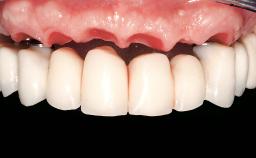

Immediate Loading of Eight Implants in the Maxilla and Six Implants in the Mandible and Final Restoration with Three-Unit and Four-Unit FDPs

Defining Characteristics Fully edentulous upper jaw to be rehabilitated with an implant-borne fixed dental prosthesis

Loading Protocol Immediate

Retention Cemented, with prosthesis margin < 3mm submucosal Cemented, with prosthesis margin < 3mm submucosal